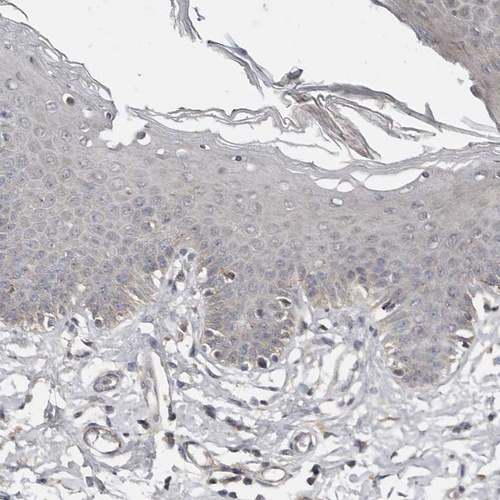

Immunohistochemical staining of human Placenta shows moderate cytoplasmic positivity in trophoblastic cells.